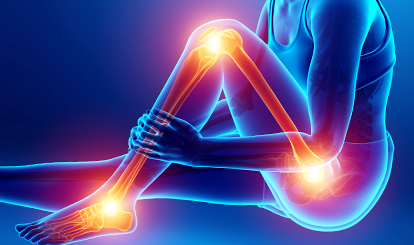

다리에서 발생한 통증이 엉덩이까지 전달되어 다리 전반적인 부위에 통증을 느낄 수 있습니다.

다리, 엉덩이가 찌릿하고 쑤시는 통증, 저림, 감각 이상

위 증상 중 한가지라도 해당된다면 “좌골신경통”일 수 있습니다.

좌골신경통이란?

좌골에 해당하는 엉덩이, 종아리, 발을 따라 나타나는 통증입니다. 신경의 감염이나 압박, 손상 등에 의해 발생할 수 있습니다.